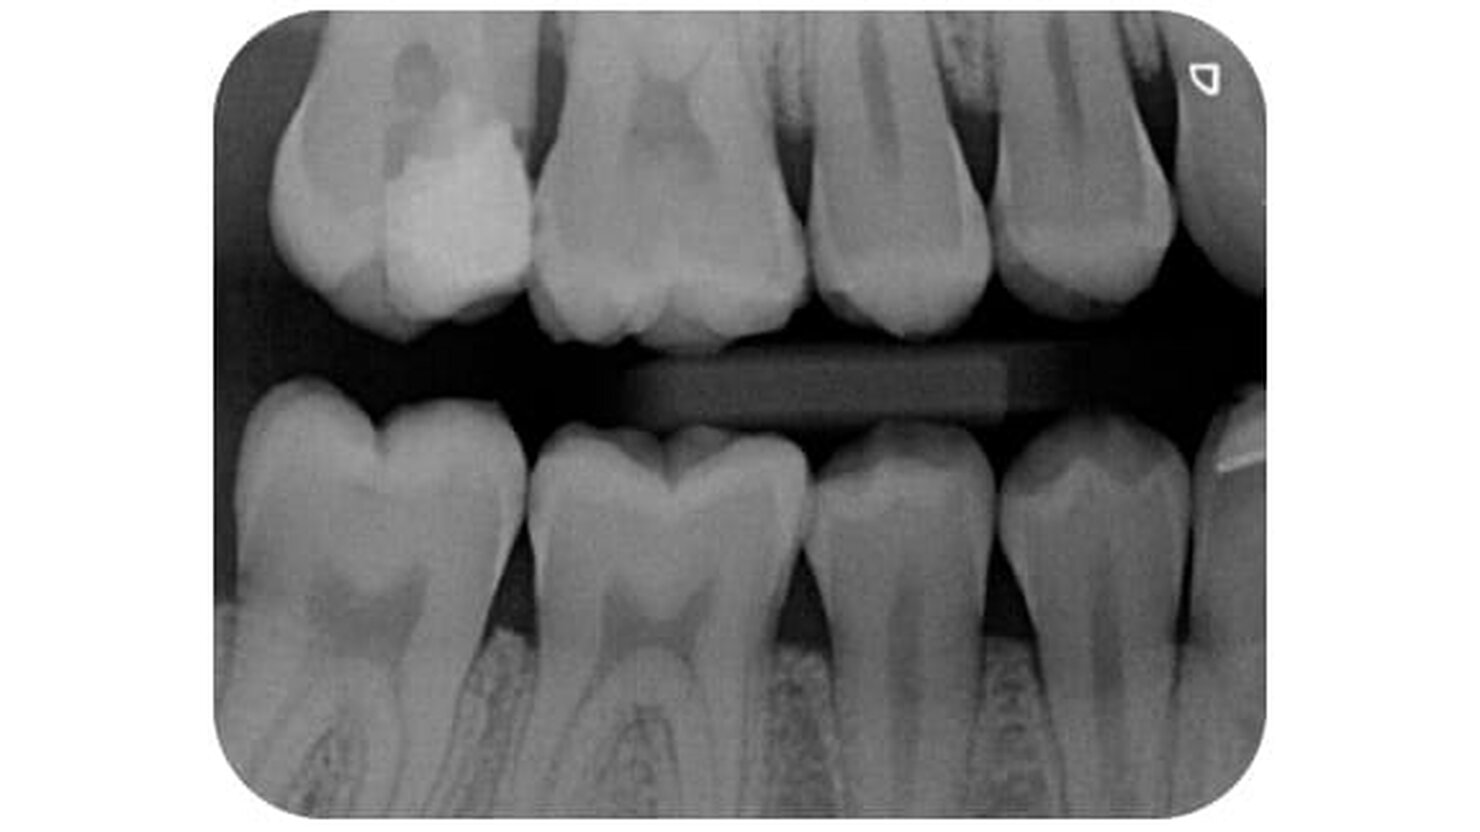

VistaScan Mini View 2.0 può visualizzare in modo sicuro, ad esempio, le lesioni cariose interprossimali e le strutture ossee più sottili.